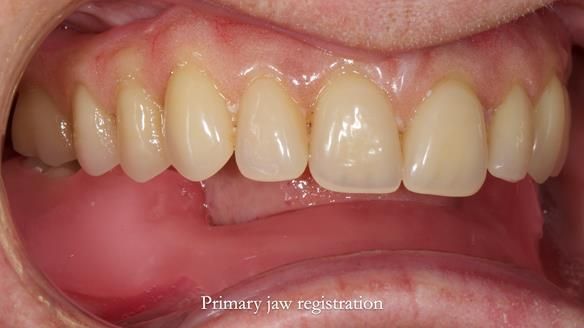

However, once Rowan and I reviewed the remaining metal crown on tooth 46, we realised it would make an ideal abutment for a gasket denture. By reshaping the lingual surface of the crown, we created an excellent gasket seal.

This approach worked far better than the proposed ring-clasp design - improving retention, comfort, and aesthetics while keeping the design clean and simple.